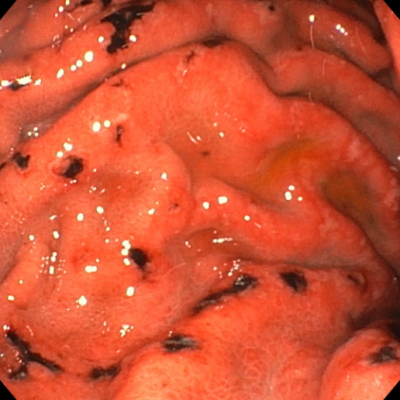

| ‚ر‚ç‚ٌگ«ˆف‰ٹ | |

|